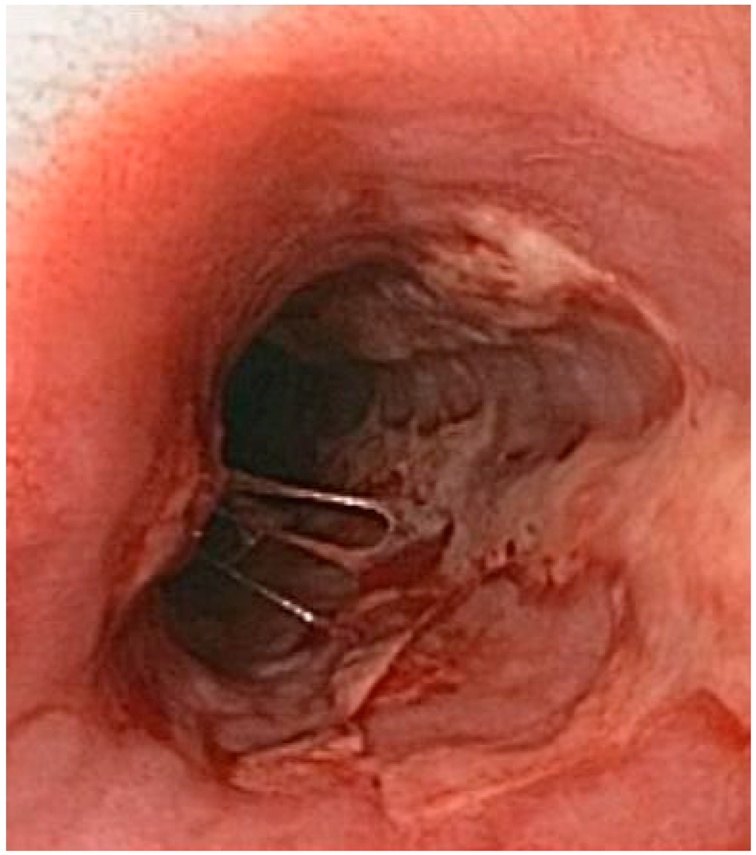

| Herpetic esophagytis | Symptoms may include pain when swallowing (odynophagia) and difficulty swallowing (dysphagia). It is often associated with impaired immune function. | ![]() 6. Herpetic esophagitis, licence CC BY-SA 3.0, adapted with concession of Donald E. Mansell, MD. |